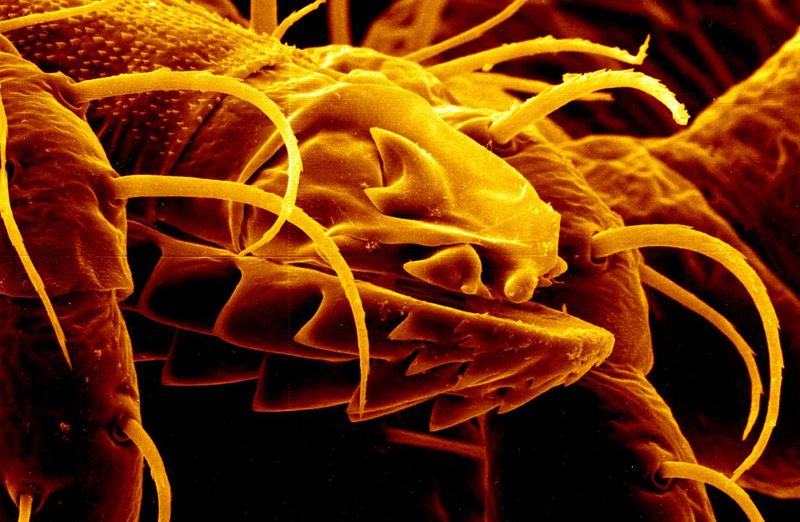

This is where the new study comes in. The researchers took 60 “human teeth that had been extracted for various reasons”, which sounds very fine and not suspicious, and gave them all amalgam fillings – that’s the silver type you probably think of as a “normal filling”. They then divided the teeth into three groups: one underwent a normal 1.5T MRI scan, one had a 7T scan, and a control group had no scan at all. After nine days brewing in vials of artificial saliva, the amount of mercury that had leaked out of the teeth was measured and recorded.

The results were … not great. Although the mean amount of mercury that leaked in a normal MRI was a little higher than the control group, the teeth that had the ultra-high MRI scan had lost nearly five times as much. The researchers also noted that problems have been found with other dental implants, with gold and platinum crowns becoming hotter under the higher magnetic fields.